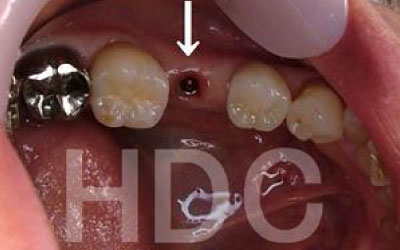

歯が抜けたままにしていたら、隣の歯が動いてしまいました。どうすればよいでしょうか?

軽度の歯のズレであれば調整や詰め物で対応可能ですが、大きく傾いてしまった場合は矯正治療や被せ物が必要になることがあります。

ズレがひどくなる前に、できるだけ早めの検査と治療を受けることをおすすめします。

少しの位置ズレであれば、噛み合わせの調整や小さな詰め物で改善することが可能です。

ただし、抜けてから数年が経過して大きく歯が傾いてしまった場合は、歯並びの矯正を行うか、歯を大きく削って被せ物をする必要があります。